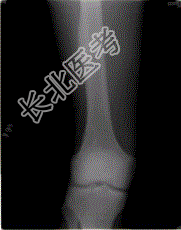

- [材料题] 患者,男性,18岁。右股外侧间歇性疼痛逐渐加重近3个月,夜间为重,X线片及CT示右股骨干下段外侧骨皮质梭形增厚硬化,增厚的骨皮质中心隐约可见小圆形低密度灶,骨髓腔未闭合,无外伤史。

- 单项选择题1.最可能的诊断是( )。

A、成骨细胞瘤

B、骨软骨瘤

C、骨样骨瘤

D、骨肉瘤

E、非骨化性纤维瘤